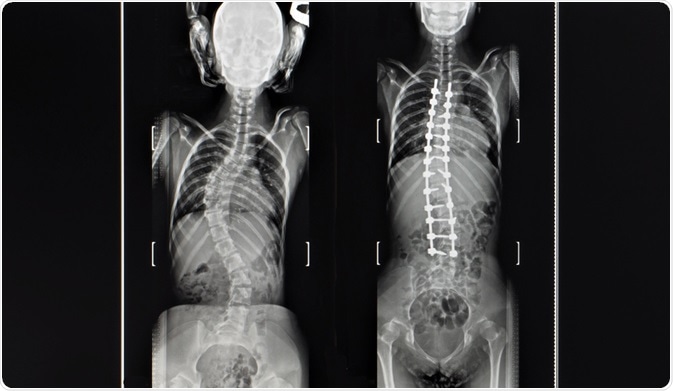

For children less than ten years old, growing rods can be inserted to help control the growth of the spine and may partially correct any existing damage. The rods will need to be monitored regularly and usually require lengthening two to three times per year as the child grows. These rods can later be removed when the adult height has been reached.

For teenagers or young adults, a spinal fusion may be needed in the treatment of scoliosis. This involves the straightening of the spine using metal rods and bone grafts to secure the spine in the correct positioning. This is considered to be a major operation and the rods typically remain in the patient's spine permanently as long as no problems arise.